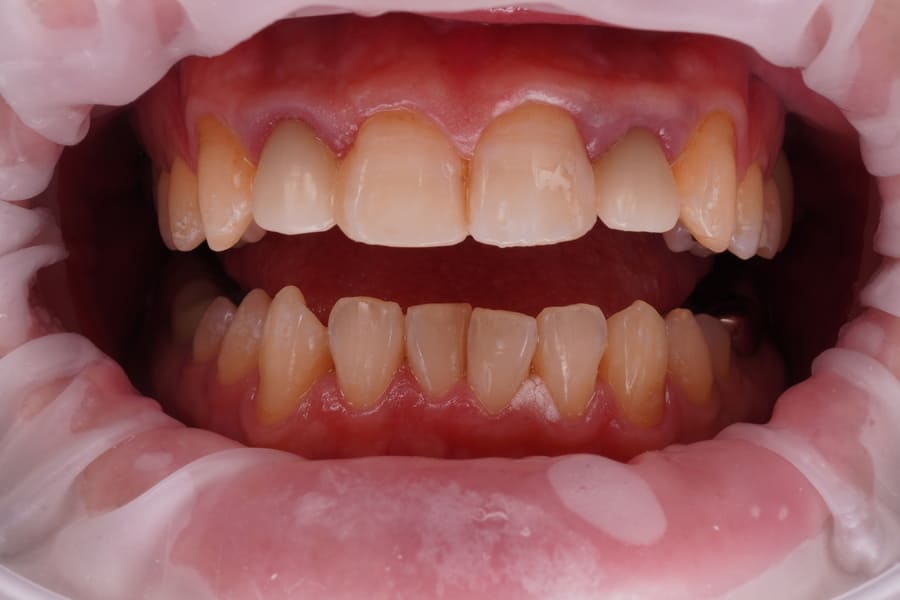

Before

After

辺縁歯肉の状態は安定しているので、

形態的・色調的問題を患者さんに確認、同意が得られたため最終補綴へ移行した。

印象採得、咬合採得を行い補綴物を製作した。

完成したオールセラミッククラウンの近遠心コンタクトの調整を行い、その後咬合チェックして咬合調整・研磨を行った。

ジルコボンドクラウンを試適して患者さんに鏡で見て頂き問題がないことを確認後、合着を行った。合着1週間後に各種チェックを行い若干の調整、研磨を行った。治療期間・回数 治療期間4週間で3回来院。 術前(2026年2月)術後(2026年3月) 費用

(自由診療となります)総額 自由診療154000円(税込み) 診査・診断・プロビジョナルレストレーション・術前術後の説明費用含む。 リスク・副作用 セラミックの破折、脱離。歯肉の退縮。根の病気。

術後の対策 補綴専門医の視点 今後、辺縁歯肉の退縮を避けるための方策を検討し患者さんと対応を共有することとした。

必ず3か月ごとの予後観察に来院していただくよう依頼した。